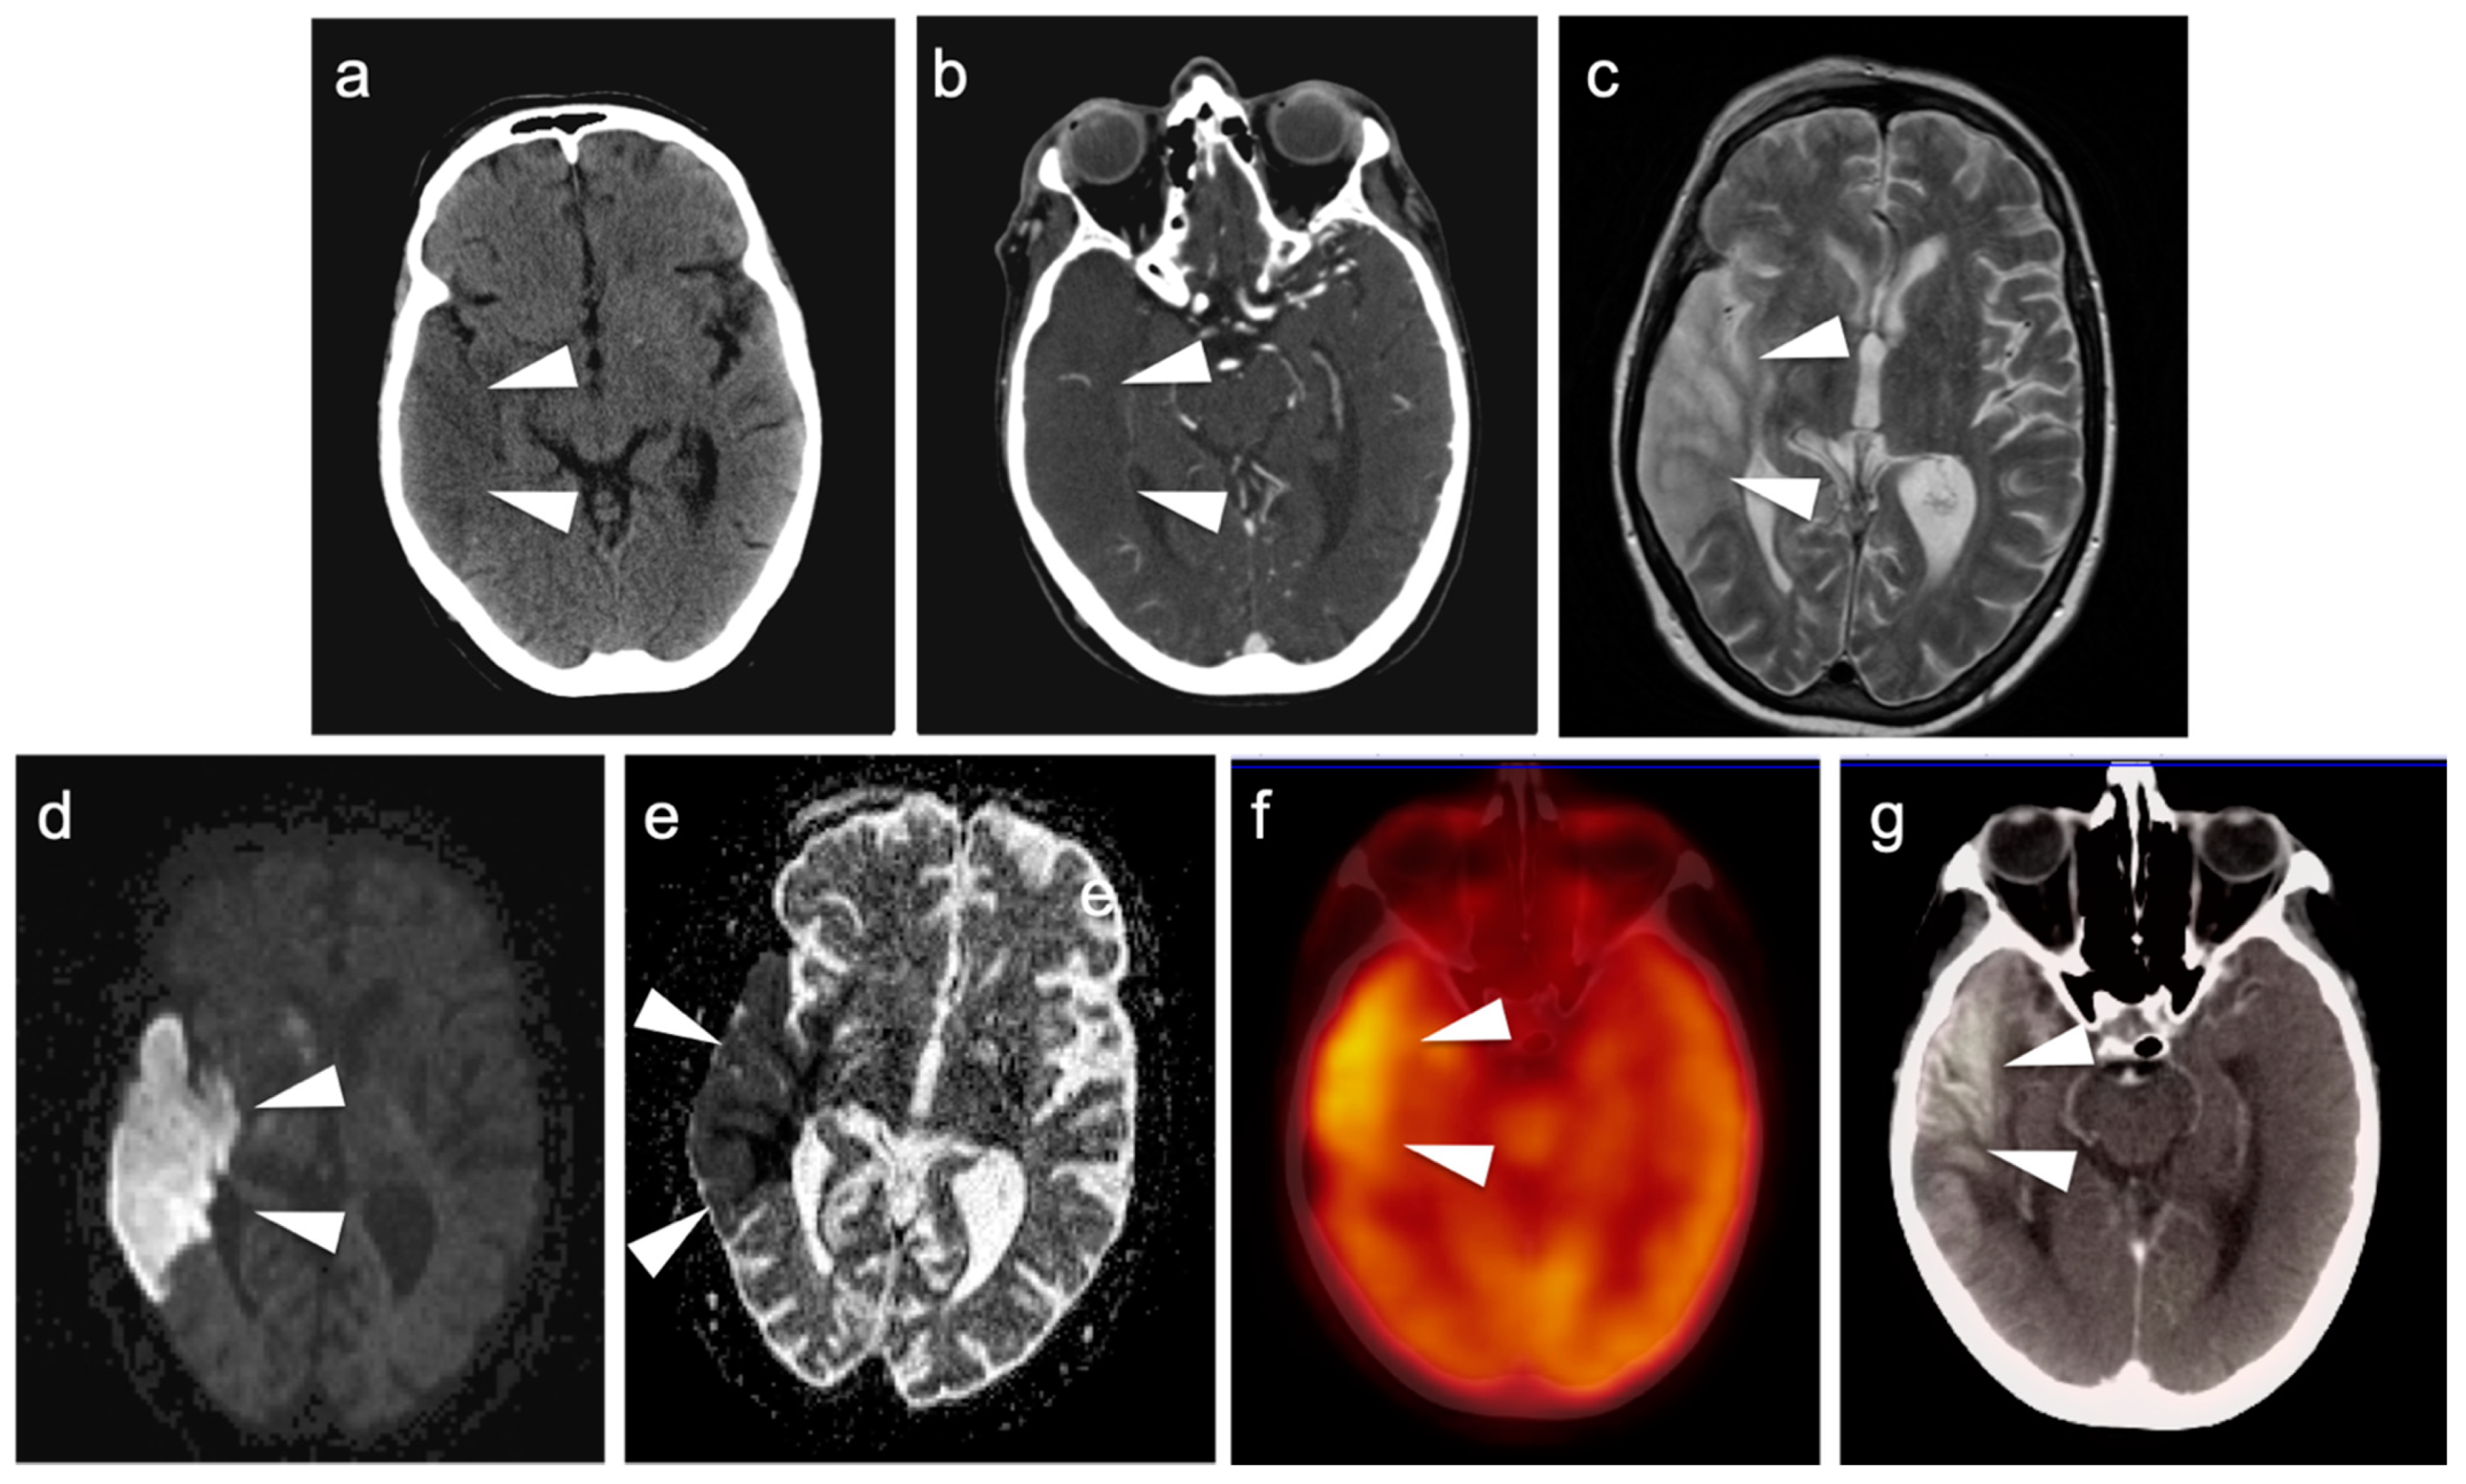

3.4. CNS Lymphoma

3.5. Brain Metastases

3.6. Response to Therapy